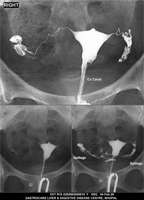

Section: HSG

Total: 49 Cases